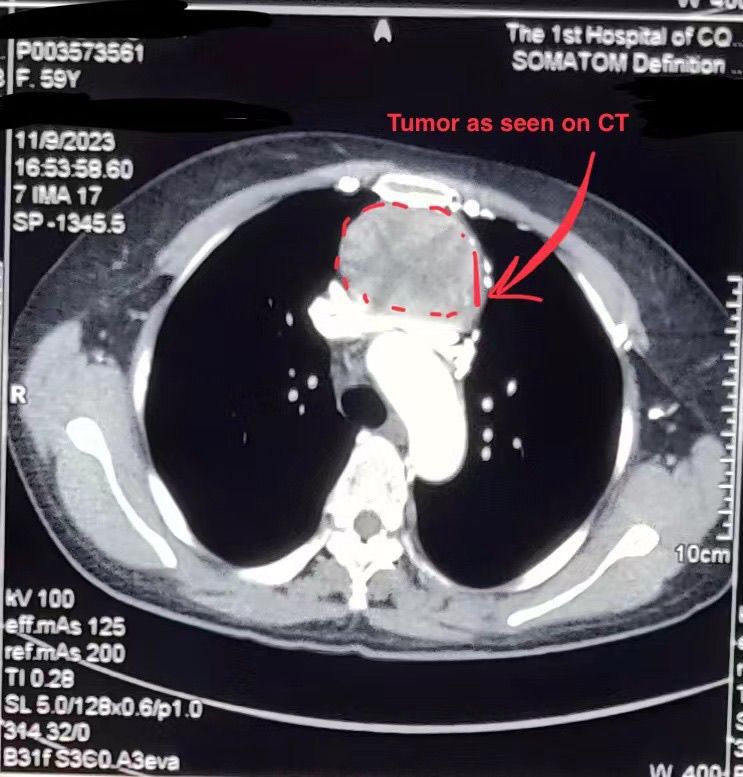

Mediastinal Tumor

CT finding of mediastinal tumor in a 59 yrs old female.